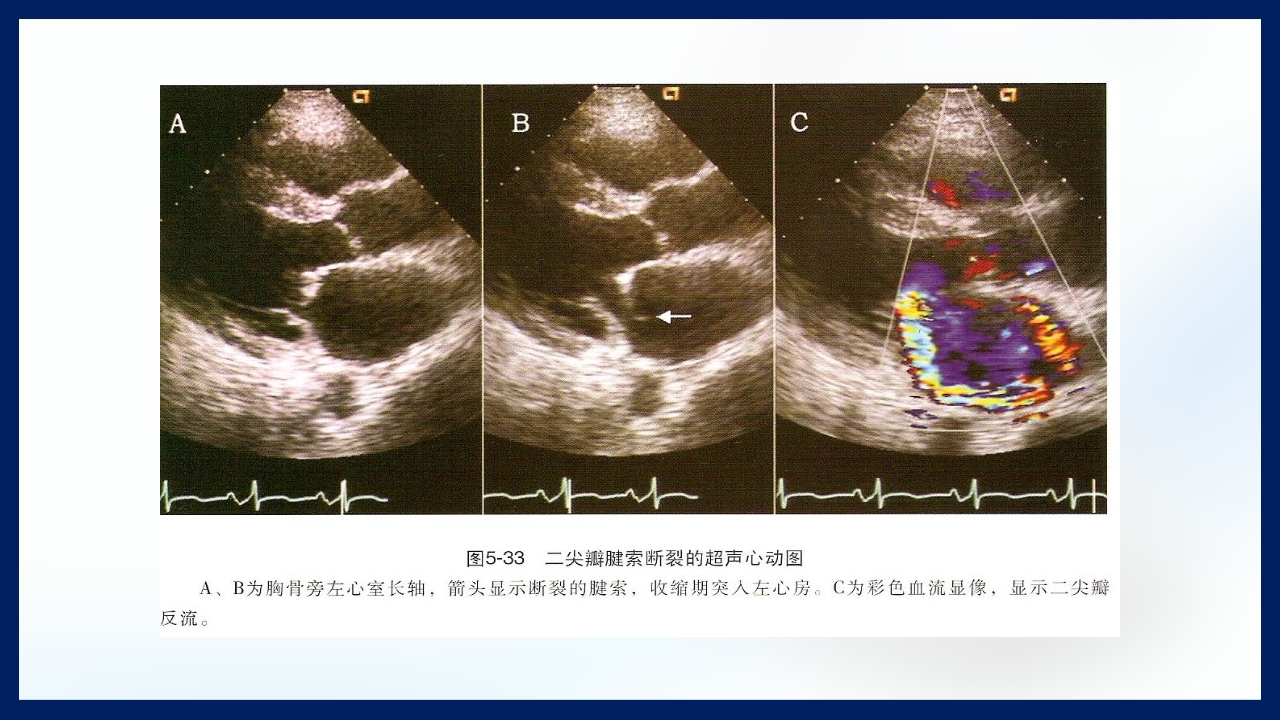

心 脏 瓣膜 医师:XXX 日期:20XX.XX.XX 讲授目的和要求 1 掌握二尖瓣和主动脉瓣膜病变的病理生理、临床表现及诊断方法。 熟悉二尖瓣和主动脉瓣膜病变的病因、鉴别诊断、并发症、治疗原则及 2 手术适应证。 3 了解瓣膜病的检查方法及治疗新进展。 心脏瓣膜病 是由于炎症、粘液样变性、退行性改变等原 因引起的单个或多个瓣膜结构的功能或结构异常,导致 瓣口狭窄及(或)关闭不全。二尖瓣最常受累,其次为 主动脉瓣。 (Rheumatic Heart Disease)简称风心病, 是风湿性炎症过程所致瓣膜损害,主要累及40岁以下人 群。 瓣膜粘液样变性和老年瓣膜钙化所致瓣膜病日渐增多。 3 瓣膜病分类 按病因分类: 风湿性、老年退行性、先天性、相对性 按受累部位和类型分: 二尖瓣狭窄、二尖瓣关闭...